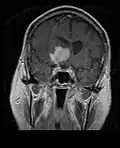

• MRI significantly underestimates extent of involvement; May appear focal on CT or MRI but parenchyma is typically diffusely involved.

• Intensely enhancing on MRI; may have a diffuse or “cotton wool” appearance on imaging.